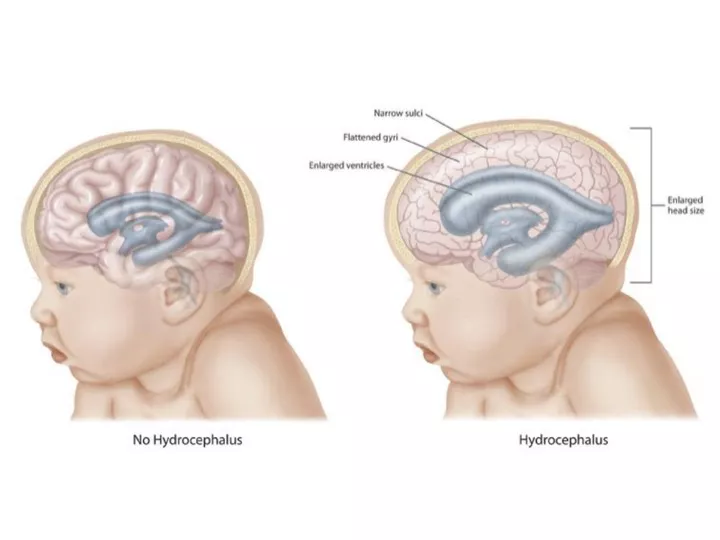

هیدروسفالی، که در زبان عامیانه به آن “آب آوردن مغز” نیز گفته میشود، یک عارضه پزشکی پیچیده و جدی است که در اثر تجمع بیش از حد مایع مغزی-نخاعی (Cerebrospinal Fluid یا CSF) در سیستم بطنی مغز ایجاد میشود. این بطنها، حفرههای به هم پیوسته در عمق مغز هستند که CSF در آنها تولید و گردش میکند. تجمع این مایع منجر به گشاد شدن بطنها و افزایش فشار داخل جمجمه میگردد که میتواند به بافت حساس و حیاتی مغز آسیب دائمی وارد کند. این وضعیت میتواند در هر سنی، از دوران جنینی تا سالمندی، رخ دهد اما در نوزادان و افراد مسن شایعتر است.

هیدروسفالی چیست؟ درک مکانیسم تجمع مایع در مغز

برای درک اینکه چرا هیدروسفالی رخ میدهد، ابتدا باید با مایع مغزی-نخاعی و سیستم پیچیده تولید، گردش و جذب آن در مغز آشنا شویم.

در یک فرد سالم، روزانه حدود ۵۰۰ میلیلیتر CSF تولید میشود و حجم کلی آن در هر لحظه حدود ۱۵۰ میلیلیتر است. این به معنای آن است که این مایع چندین بار در روز به طور کامل جایگزین میشود. CSF در یک چرخه مداوم از بطنهای جانبی به بطن سوم، سپس از طریق یک کانال باریک به نام مجرای سیلویوس (Aqueduct of Sylvius) به بطن چهارم و در نهایت به فضای اطراف مغز و نخاع جریان مییابد. در انتها، این مایع از طریق ساختارهای میکروسکوپی به نام پرزهای عنکبوتیه (Arachnoid Villi) به سینوسهای وریدی بزرگ مغز بازجذب میشود و به جریان خون بازمیگردد. هیدروسفالی زمانی اتفاق میافتد که این تعادل ظریف به هم میخورد:

- انسداد (Obstruction): شایعترین علت؛ یک مانع فیزیکی مانند یک تومور، کیست یا تنگی مادرزادی (مانند تنگی مجرای سیلویوس) مسیر گردش CSF را مسدود میکند.